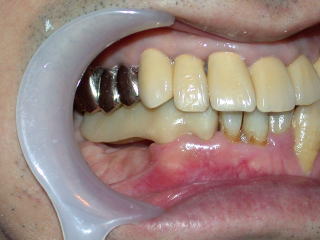

平成20年3月、インプラントの植立を行いました。

上下の隙間(補綴スペース)や近遠心、頬舌関係を良く調べます。

顎の上下関係、全体の位置付けも重要です。

目視で良く確認、レントゲンで位置をさらに良く確認します。

インプラントの位置が、良い位置に植立されたのを確認し、4糸縫合しました。

インプラント固定用の仮歯を装着し、抗生物質などを処方し、インプラント植立を終了します。